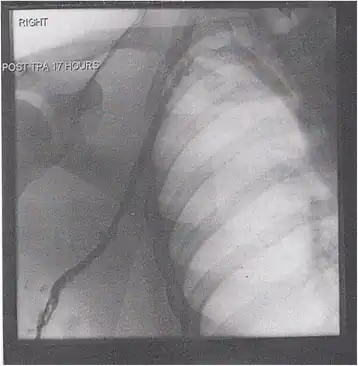

Thrombolysis is the injection of an enzyme into the veins to dissolve blood clots, and while this treatment has been proven effective against the life-threatening emergency clots of stroke and heart attacks, randomized controlled trials[139][140][141] have not established a net benefit in those with acute proximal DVT.[5][142] Drawbacks of catheter-directed thrombolysis (the preferred method of administering the clot-busting enzyme[5]) include a risk of bleeding, complexity,[l] and the cost of the procedure.[125] Although, while anticoagulation is the preferred treatment for DVT,[125] thrombolysis is a treatment option for those with the severe DVT form of phlegmasia cerula dorens (bottom left image) and in some younger patients with DVT affecting the iliac and common femoral veins.[12] Of note, a variety of contraindications to thrombolysis exist.[125] In 2020, NICE kept their 2012 recommendations that catheter-directed thrombolysis should be considered in those with iliofemoral DVT who have "symptoms lasting less than 14 days, good functional status, a life expectancy of 1 year or more, and a low risk of bleeding."[138]

A mechanical thrombectomy device can remove DVT clots, particularly in acute iliofemoral DVT (DVT of the major veins in the pelvis), but there is limited data on its efficacy. It is usually combined with thrombolysis, and sometimes temporary IVC filters are placed to protect against PE during the procedure.[143] Catheter-directed thrombolysis with thrombectomy[141] against iliofemoral DVT has been associated with a reduction in the severity of post-thrombotic syndrome at an estimated cost-effectiveness ratio of about $138,000[m] per gained QALY.[144][145] Phlegmasia cerulea dolens might be treated with catheter-directed thrombolysis and/or thrombectomy.[19][143]

In DVT in the arm, the first (topmost) rib can be surgically removed as part of the typical treatment when the DVT is due to thoracic outlet syndrome or Paget–Schroetter syndrome. This treatment involves initial anticoagulation followed by thrombolysis of the subclavian vein and staged first rib resection to relieve the thoracic outlet compression and prevent recurrent DVT.[146]